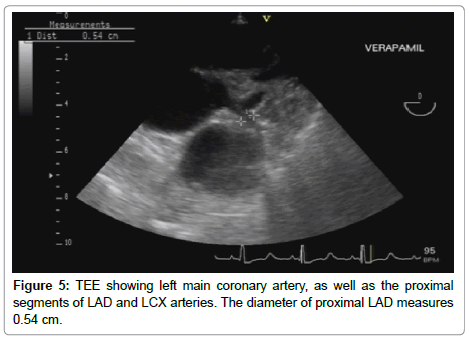

The probe was introduced till about 30 cm from the incisor teeth at which level the aortic cusps could be seen (basal short axis view at the level of the aortic valve). The probe was then withdrawn slowly till the opening of the left main coronary artery was clearly visible. Fine adjustments with rotation and flexion were made to obtain an optimal image of the left anterior descending coronary artery. The opening of the left main coronary artery could be seen at the 2 o’clock position of the aortic ring. The bifurcation of the left main coronary artery was observed as Y-shaped, with the left circumflex artery appearing as continuation of the left main coronary artery, and the left anterior descending coronary artery lying in a plane almost perpendicular to that of the left main and left circumflex coronary arteries.

Measurement of the diameter of the left anterior descending artery was documented in centimeters by two-dimensional mode.

Pulsed Wave (PW) sample volume was placed over the proximal portion of the LAD, and the direction of the sample volume was made as parallel as possible to that of the LAD, followed by spectral recording of the flow velocity, with assessment of the following parameters: Peak systolic and diastolic velocities (m/sec); Systolic, diastolic, and total velocity time integrals (VTI) (cm). The coronary blood flow parameters (systolic, diastolic and total) were calculated using the following formula: Coronary flow (cm/min)=Coronary cross section area X Velocity time integral X heart rate. Following Intravenous injection of verapamil bolus in a dose of 0.1 mg/kg, heart rate, blood pressure and all the previously mentioned measurements were reassessed within 5 minutes of verapamil administration (Figures 1-6).